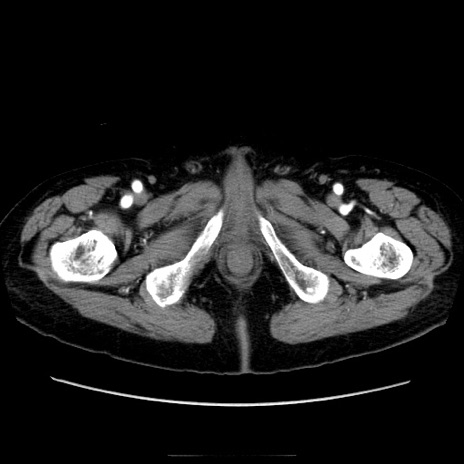

症例21(横断像)

【症例】70歳代男性

【主訴】腹痛

【現病歴】肝硬変・肝細胞癌にてかかりつけの方。約9時間前に食後より腹痛出現。症状が徐々に増悪し、嘔吐出現したため来院。

【既往歴】肝硬変、肝細胞癌(RFA、TACE後)

【身体所見】意識清明、表情苦悶様、BT 36℃、BP 129/78mmHg、P 88bpm、SpO2 97%(RA)、右上腹部から心窩部にかけて圧痛あり、反跳痛なし、筋性防御あり。

【データ】WBC 5800、CRP 0.16